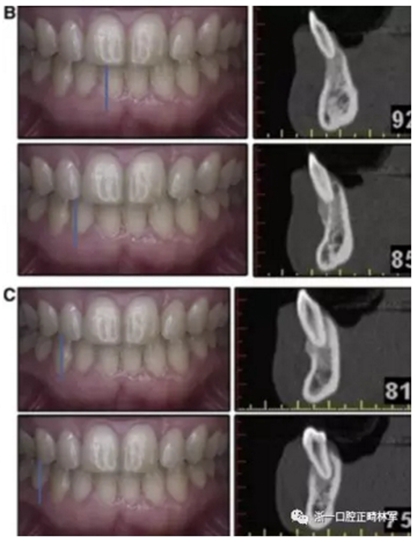

患者決定采用非手術(shù)治療方法,側(cè)貌沒有任何預(yù)期的變化。治療后面部照片(圖5)顯示她改善的微笑和側(cè)貌,包括尖牙保護合。由于先天性第一前磨牙缺失,右磨牙關(guān)系為III類。治療后牙齒石膏模型(圖6)顯示實體牙齒交錯排列情況,并且全景X線片顯示可接受的牙根平行度而且沒有牙根吸收表現(xiàn)(圖7)。最終的頭影測量片(圖7)證實了面部評估,并且描跡圖顯示深覆蓋的改善,同時保持上頜切牙位置并通過測量ANB角度和Wits評估改善骨性II級關(guān)系(表)。治療前后的疊加圖顯示由于下頜切牙前傾的增加改善了下唇平衡(圖8)。如相關(guān)治療計劃所預(yù)測的那樣,B點出現(xiàn)。A進行牙科錐形束計算機斷層掃描以記錄下頜前牙區(qū)的骨質(zhì)變化。如預(yù)期的那樣,由于治療導(dǎo)致該區(qū)域的骨量增加(圖9)。